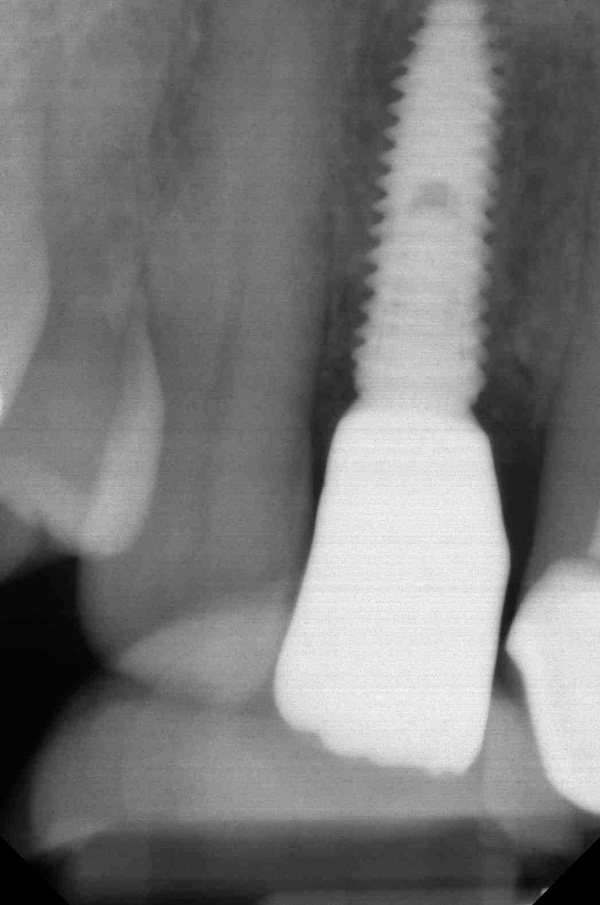

Fig 10. Periapical radiograph showing implant placement with abutment in place for fabrication of provisional crown.

Figure 10

When placing an implant in the esthetic zone, ideal 3-dimensional positioning, including mesio-distal, apico-coronal, and orofacial dimensions, is essential to achieve favorable esthetic outcomes, regardless of the implant system used (Figure 6).45 With respect to the orofacial dimension, implants should be placed in a more palatal or lingual position to allow the presence of at least 2 mm of buccal bone thickness from the implant buccal shoulder.45,46 When the distance of the buccal bone wall and implant buccal shoulder is < 2 mm, a significantly higher incidence of midfacial recession has been previously reported.3,12 Placement of bone graft (Figure 7) and immediate restoration (Figure 8 and Figure 9) at the time of implant placement has also been suggested to increase peri-implant soft-tissue height and thickness.51 In the apico-coronal dimension, the implant head should be at least 3 mm apical to an imaginary line connecting the CEJ of the adjacent teeth and 1 mm to 2 mm apical to the interproximal and crestal bone to ensure a proper implant emergence profile and facilitate proper implant restoration (Figure 10). Regarding the horizontal implant–tooth distance, implants should be placed no closer than 1.5 mm from the adjacent root surface to minimize resorption of the interproximal alveolar crest, which causes a reduction in the papillary height.46,52